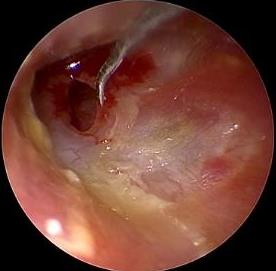

• 耳内镜下耳屏软骨-软骨膜鼓膜修补术后的短期疗效观察

摘要:目的 探讨耳内镜下耳屏软骨-软骨膜鼓膜修补术后的短期疗效。方法 回顾性分析2019年9月-2022年8月该院收治的78例鼓膜穿孔患者的临床资料,患者均采用耳内镜下鼓膜修补术。术后随访3个月,观察鼓膜形态和穿孔愈合情况,记录内镜图像、干耳时间、术前术后听力及耳鸣情况,以及外耳道狭窄等并发症的发生率。结果 术后3个月,鼓膜穿孔愈合率为97.44%(76/78),愈合良好,平均气导听阈较术前明显改善,气骨导间距较术前明显缩小,耳鸣较术前明显改善,差异均有统计学意义(P<0.05)。干耳时间为(4.21±1.12)周。术后出现肉芽5例,再穿孔2例,真菌感染2例,术腔感染、耳屏感染、外耳道狭窄和切口瘢痕各1例,所有患者术后均未发生面神经麻痹和感音神经性聋等严重并发症。结论 耳内镜下耳屏软骨-软骨膜鼓膜修补术是一种安全、有效的手术方法。根据术后愈合规律、内镜下鼓膜和外耳道形态特征,可为鼓膜修补术后正常中耳转归和并发症的诊疗,提供临床参考。